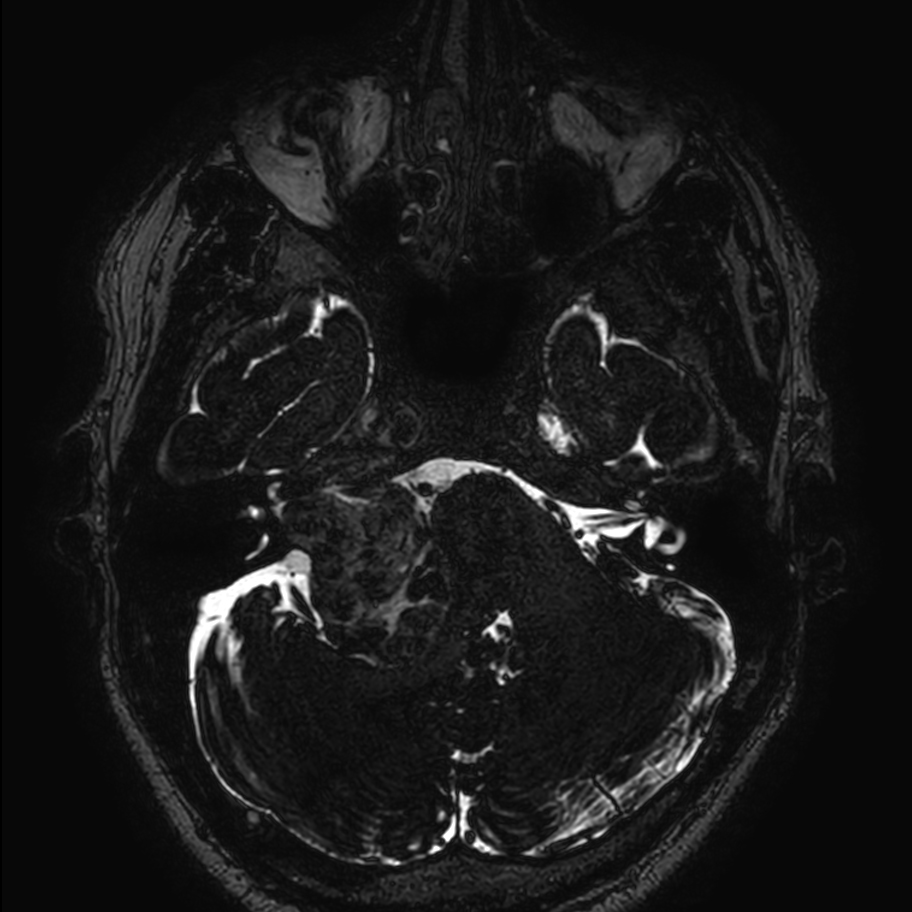

Patient with a brain (IAC) lesion. Compressed SENSE is used to shorten the scan time of the high resolution clinical scans, whilst MultiBand SENSE is used to reduce the scan time of the functional (DTI) scan.

Axial 3D T2w TSE DRIVE